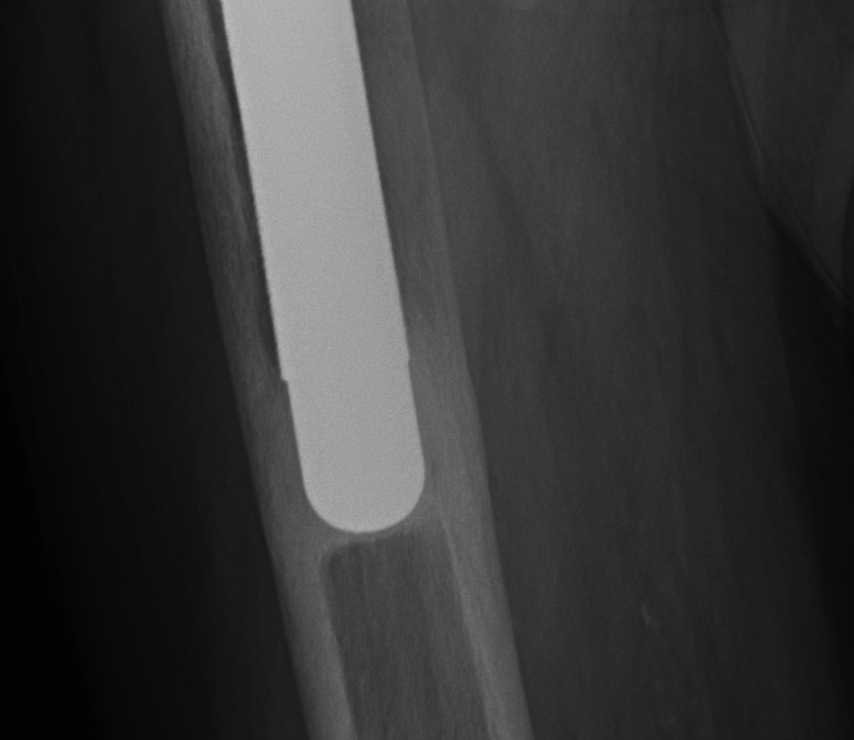

Uncemented femur

Engh classification

Types based on presence of radiolucent lines (RLL)

III Unstable fibrous ingrowth

A.  Component migration

B.  Progressive increase RLL

- divergent RLL

C.  Pedestal formation (bony hypertrophy at tip)

THR Uncemented Subsidence